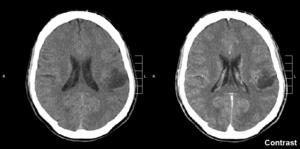

Glioma in the left parietal lobe (brain CT scan), WHO grade 2.